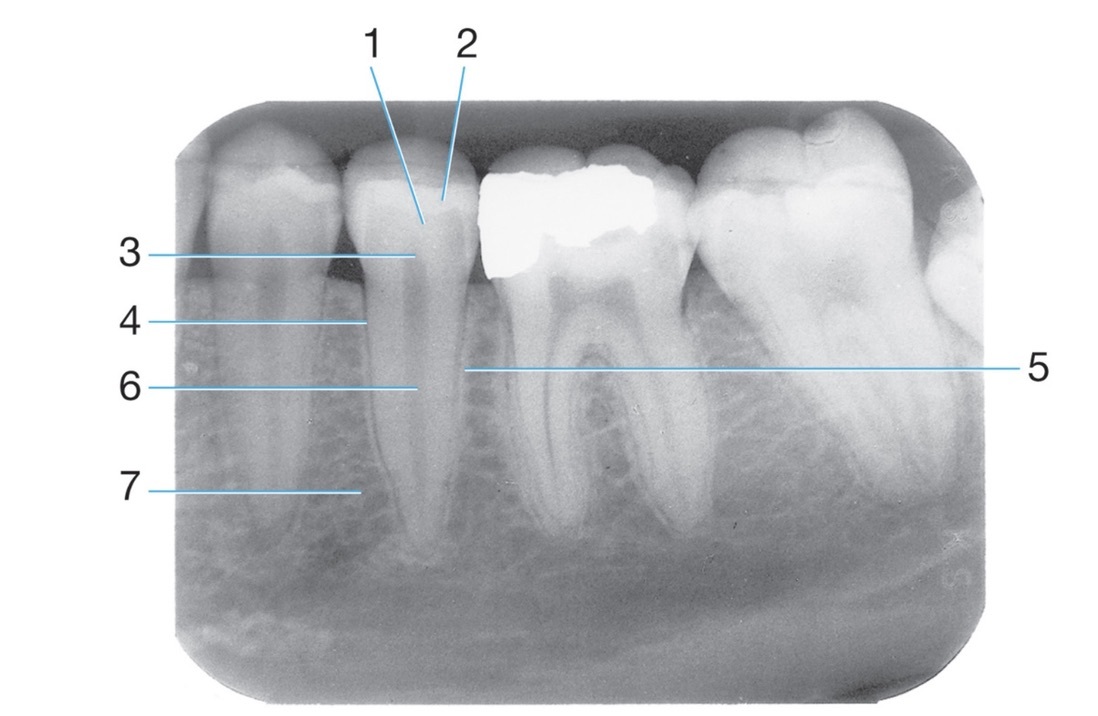

Amalgam

Dental base

PDL space

2.

Mylohyoid ridge

4

6.

Post and core